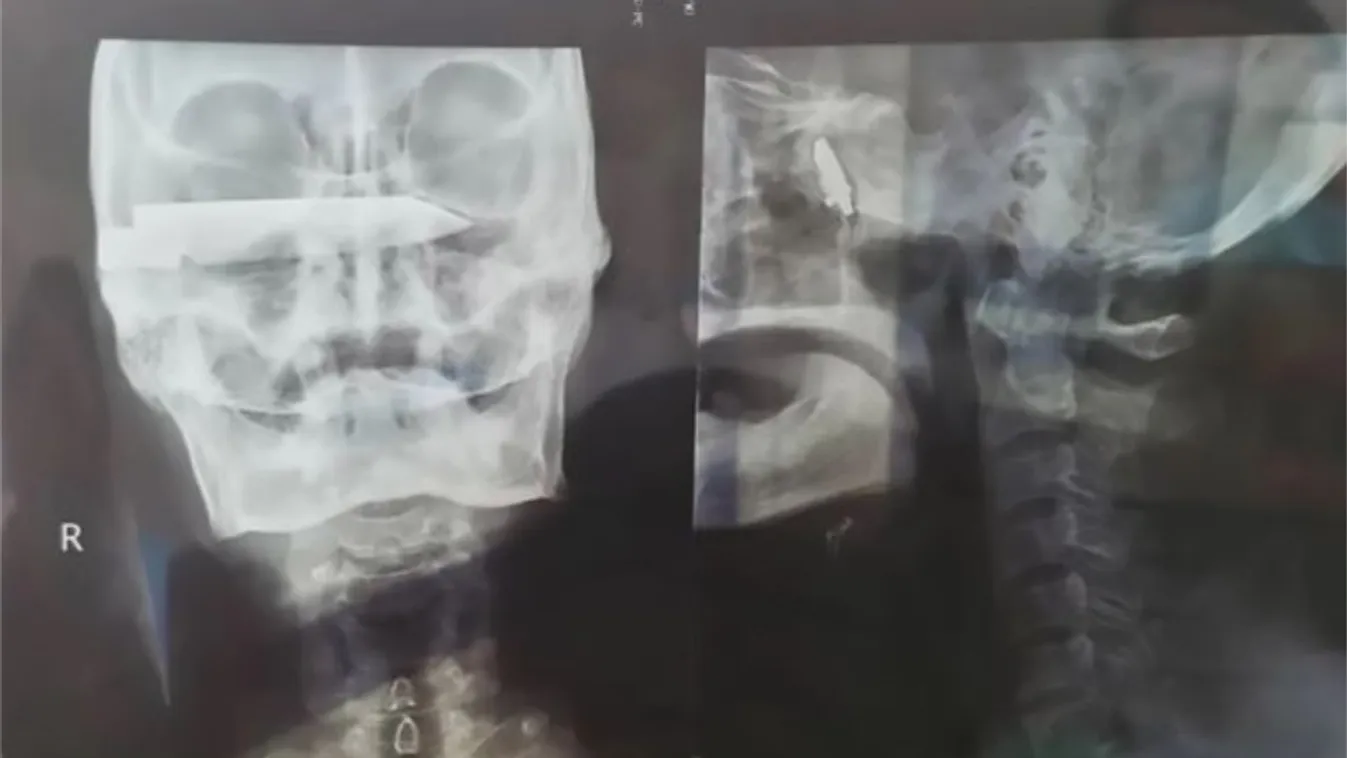

KOMPOST 2020. 04. 13. Még az orvosok is sokkot kaptak, amikor meglátták, mi volt a férfi koponyájában 26 évig Még az 1990-es években támadta meg egy rabló, azóta a tárggyal a koponyájában élt a férfi.